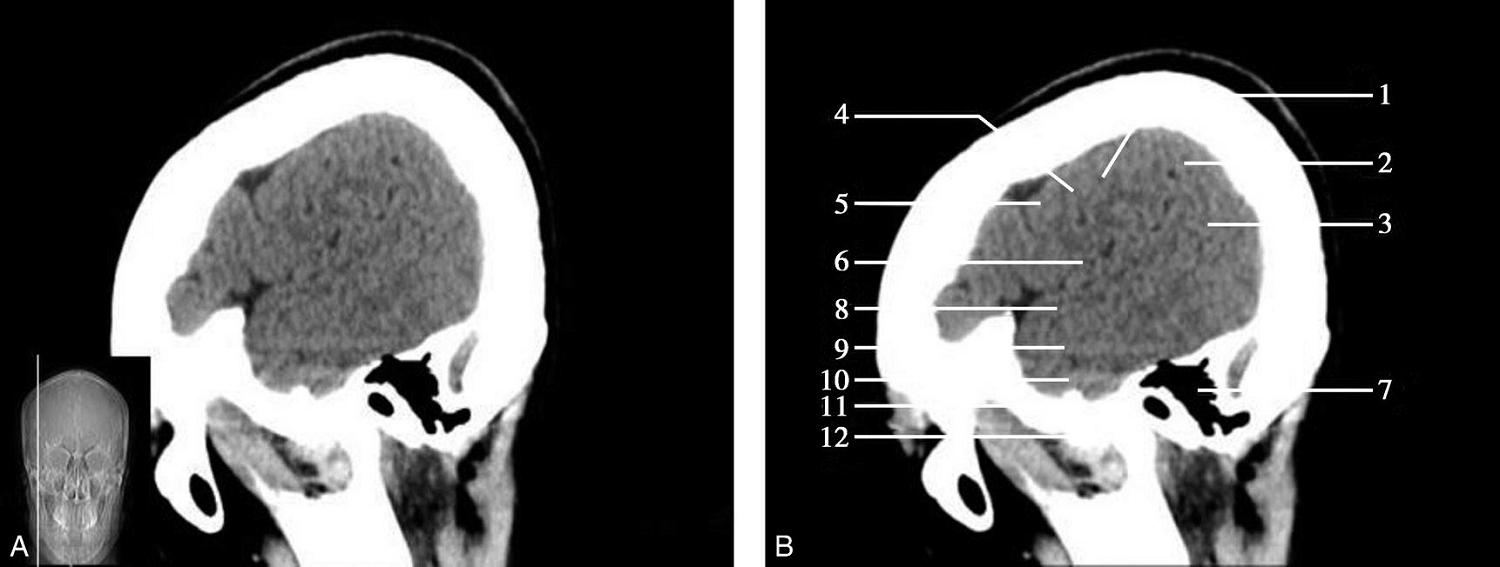

CT血管成像(CT angiography,CTA及CT venography,CTV)通过三维重建技术可显示颅内动静脉的走行、血管壁及血管周围等情况(图1-2-73~图1-2-75)。

基底动脉开窗畸形的发生机制被认为是胚胎第5周时成对的胚胎性神经动脉融合障碍,或为原始侧动脉残留所致(图1-2-78)。

图1-2-78 基底动脉开窗畸形(箭)

永存三叉动脉是颈内动脉海绵窦段与基底动脉之间的胚胎性吻合,为颈内动脉系统与椎基底动脉系统之间最常见的异常交通,是根据它伴行的颅神经而命名的。其他异常吻合包括永存听动脉、永存舌下动脉及永存寰前节间动脉(图1-2-79)。

图1-2-79 永存三叉动脉

A、B.异常吻合支沟通至右侧海绵窦(箭);基底动脉(长箭)